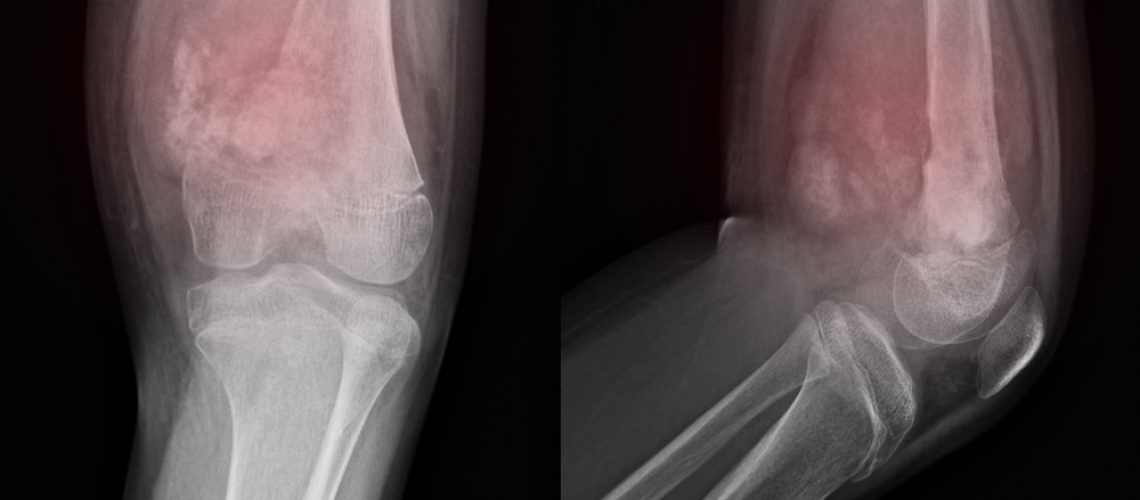

Cirurgia para osteossarcoma

A cirurgia é uma etapa fundamental para o tratamento desse tipo de câncer. Ela é recomendada para quase que todas as situações. Suas fases incluem:- realizar biopsia com o intuito de fazer o diagnóstico do câncer;

- promover o tratamento cirúrgico para a remoção do tumor.